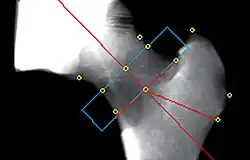

Clinically, QCT is used at the hip to produce areal BMD measurements and T-Scores that are equivalent to DXA measurements.[5] The exam can be done without particular attention to the positioning of the patient's limbs because the software allows the hip anatomy to be manipulated after the image is captured, allowing the exam to be performed on patients with arthritic hips who may find traditional exams uncomfortable.

At the hip, a DXA-equivalent T-score may be calculated for comparison to the WHO classification at the proximal femur as normal, osteopenia (T-Score < -1.0 and > -2.5) or osteoporosis (T-Score < -2.5).[17] This T-Score may also be used for fracture risk probability calculation in the WHO FRAX tool[18] with "T-Score" as the appropriate DXA setting.